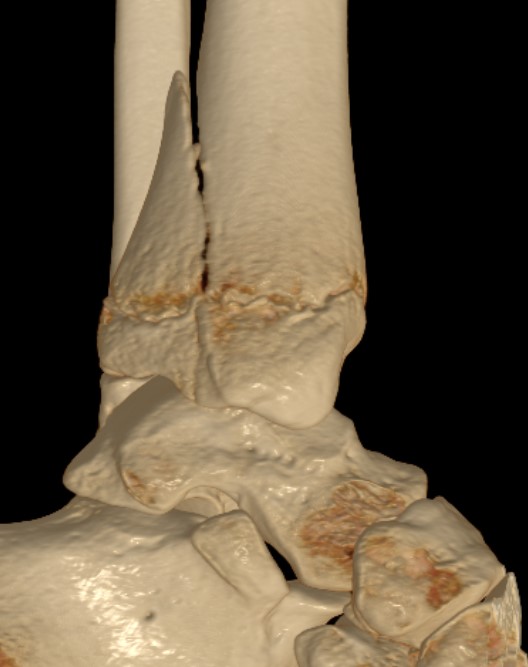

Triplanar Fracture

Definition

Fracture in coronal, sagittal and transverse planes

- crosses epiphysis

- passes through growth plate

- extends into metaphysis

Xray

AP xray: Salter-Harris type III / Tillaux

Lateral xray: Salter-Harris Type II

CT

Coronal images: Salter-Harris type III

Sagittal images: Salter-Harris type II

Axial images: 3 point star